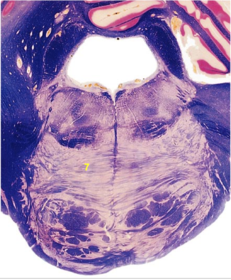

| Nucleus gracilis | |

| Accessory nucleus | |

| Medial longitudinal faciculus | |

| Pyramidal decussation | |

| Medullary pyramids | |

| Anterior spinocerebellar tract | |

| ALS | |

| Posterior spinocerebellar tract | |

| Spinal tract of V | |

| Spinal nucleus of V | |

| Nucleus cuneatus | |

| Fasciculus cuneatus | |

| Fasciculus gracilis | |

| Central canal | |

| Internal acruate fibers | |

| Lateral (external/accessory) cuneate nucleus | |